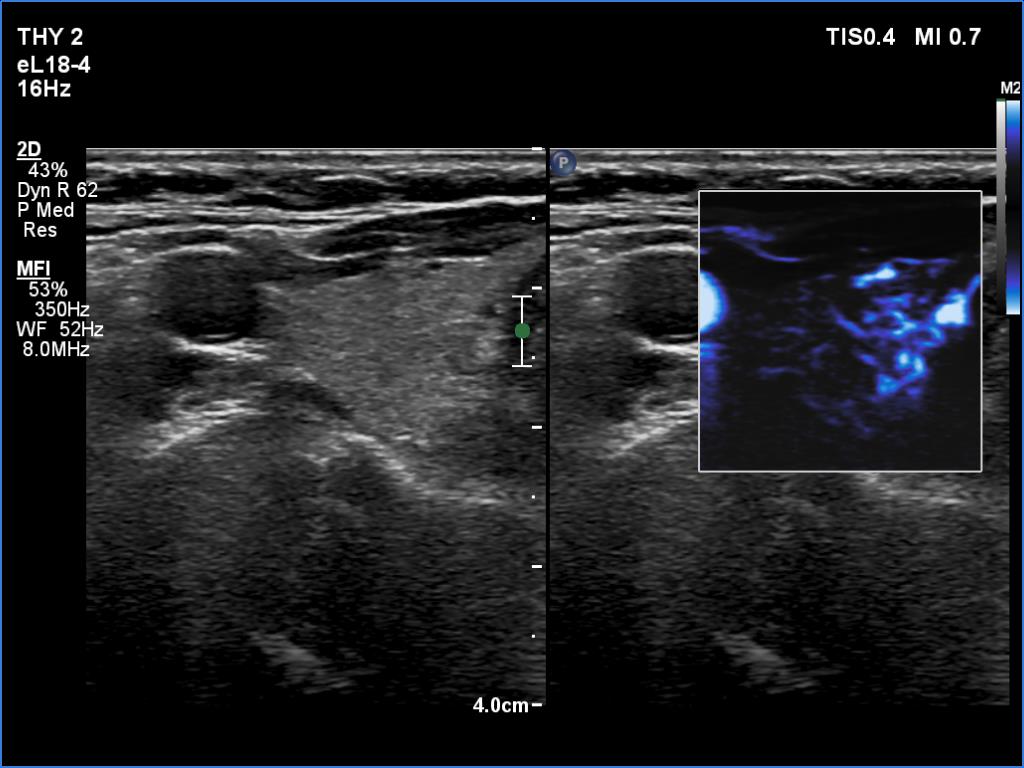

Right lobe, longitudinal scan

Right lobe, transverse scan, microflow imaging. The vascularity is not specific.